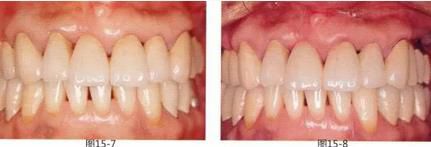

圖15-7  術后5個月開始制作的最終修復體,佩戴最終修復體后經(jīng)過2年的狀態(tài)。

圖15-8  術后8年。